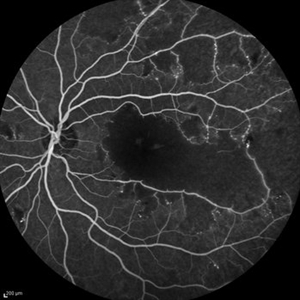

Behcet's Disease Behcet's DiseaseMar 13 2013 by Hamid Ahmadieh, MD Mid phase FA of the right eye of a 23-year-old man with retinal vasculitis and branch retinal vein occlusion (BRVO) due to Behcet's disease . Photographer: Solmaz Shahmohammad, Negah Eye Center, Tehran Imaging device: Heidelberg Spectralis Condition/keywords: branch retinal vein occlusion (BRVO), retinal vasculitis